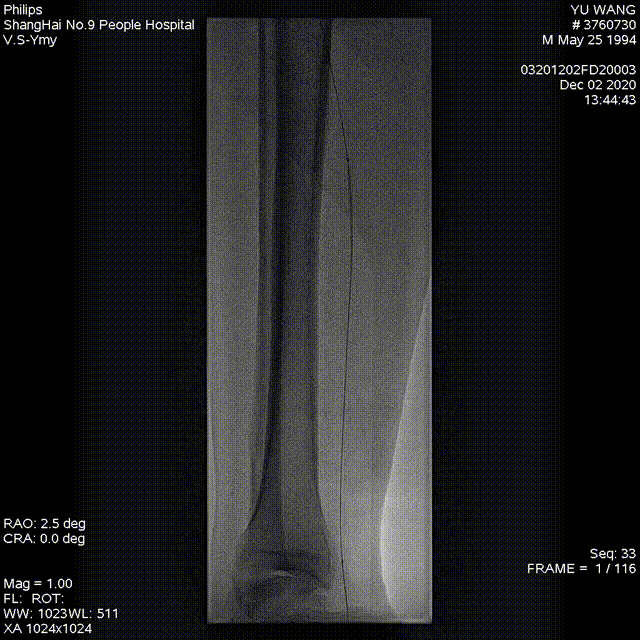

★ 激光消融

图:使用2.3mm导管,参数设置从45mj/mm²、45Hz开始,逐步增加至60mj/mm²、60Hz。

★ 球囊扩张

依次使用不同规格球囊进行扩张

Saber 2--200mm球囊

Saber 5--300mm球囊

Reewarm 5--220mm球囊

Saber 2.5--150mm球囊

★ 术后结果

血管造影显示管腔明显改善,血流恢复良好

图:术后造影